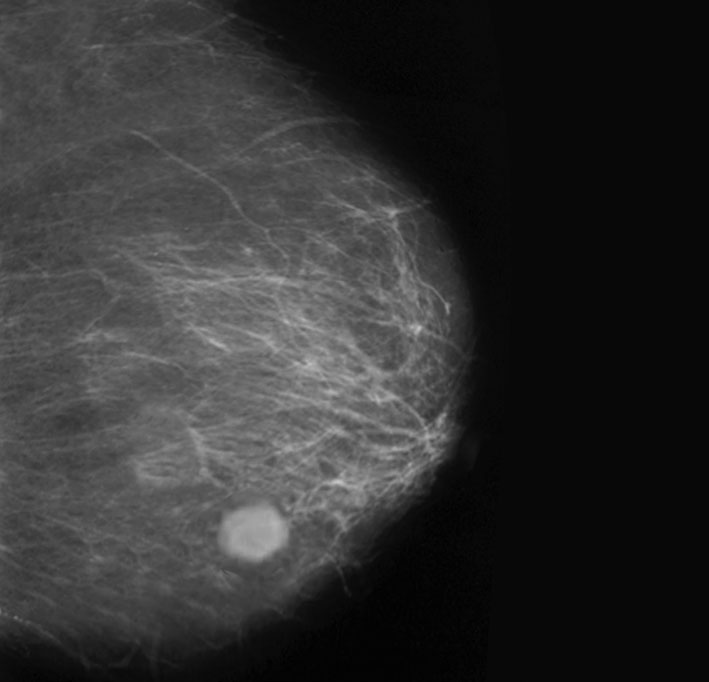

• Hidemi Furusawa, M.D. of the Breastopia Clinic in Japan treated 72 patients with early breast cancer using focused ultrasound followed by standard radiation. With a median follow-up of 68 months, there were no distant recurrences and one local invasive recurrence after seven years, suggesting that focused ultrasound has the potential to replace surgery as a local treatment for early breast cancer.